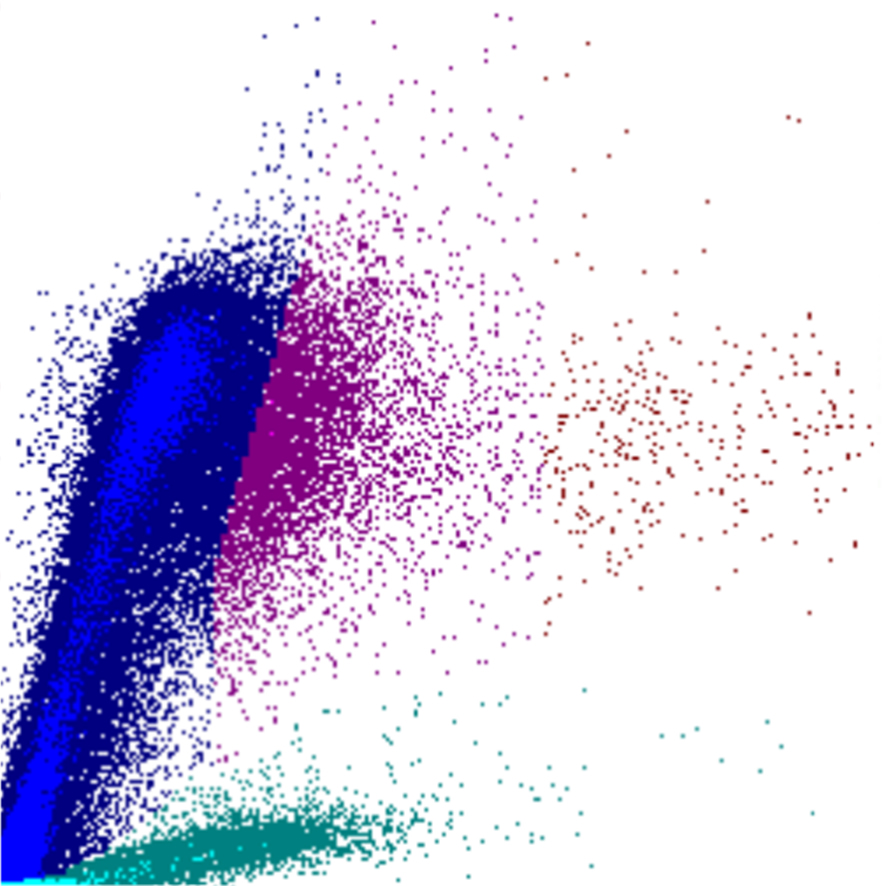

Dans cette section, vous trouverez une explication des diagrammes de dispersion (également appelés scatter ou scatterplots) issus de la série Sysmex XN/XR, avec un accent sur les canaux WDF, WNR et RET. Les scatterplots constituent la base de l’analyse différentielle des leucocytes et offrent une visualisation des populations cellulaires et de leurs anomalies.

Dans le Sysmex XN, les cellules sont analysées par cytométrie en flux. Après l’ajout de réactifs spécifiques, les cellules sont fixées, lysées ou colorées selon le canal. Les cellules individuelles traversent ensuite un faisceau laser, où plusieurs propriétés physiques sont mesurées :

• Forward scatter (FSC) – lié à la taille cellulaire

• Side scatter (SSC) – lié à la complexité interne

• Side fluorescence (SFL) – lié au contenu en acides nucléiques

Selon les paramètres représentés l’un par rapport à l’autre, la combinaison de ces signaux détermine la position de chaque cellule sur le diagramme de dispersion. Cela génère des clusters caractéristiques pour les populations cellulaires normales et des motifs reconnaissables en cas d’anomalies.